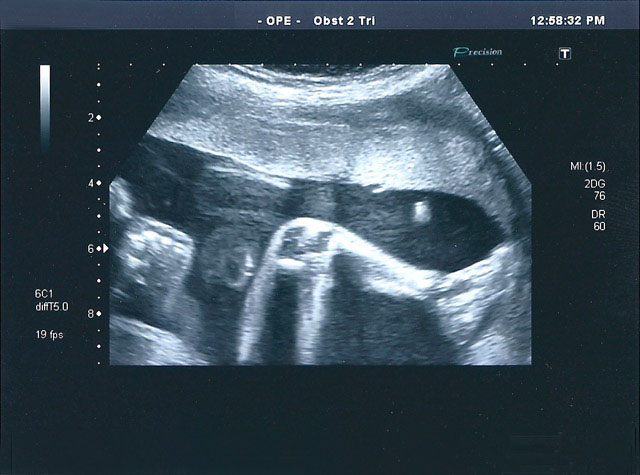

inicialexames a clinicapreçáriogaleriaFAQcontactos